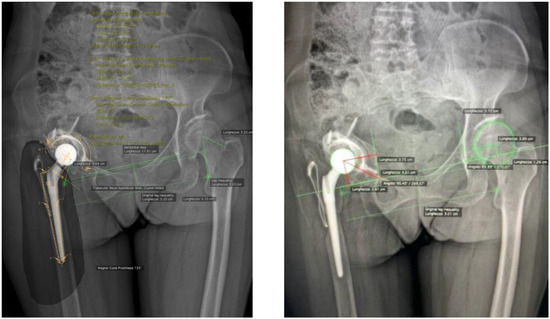

| LLD (cm) | 2.0 ± 1.2 | 0.6 ± 0.6 | p < 0.001 |

| Average COR vertical position (cm) | 3.5 ± 1.7 | 2.0 ± 0.7 | p < 0.05 |

| Average COR horizontal position (cm) | 3.9 ± 1.5 | 3.2 ± 0.5 | p < 0.05 |

| Acetabular component abduction angle | 59.7 ± 29.6 | 46.0 ± 3.9 | p < 0.05 |